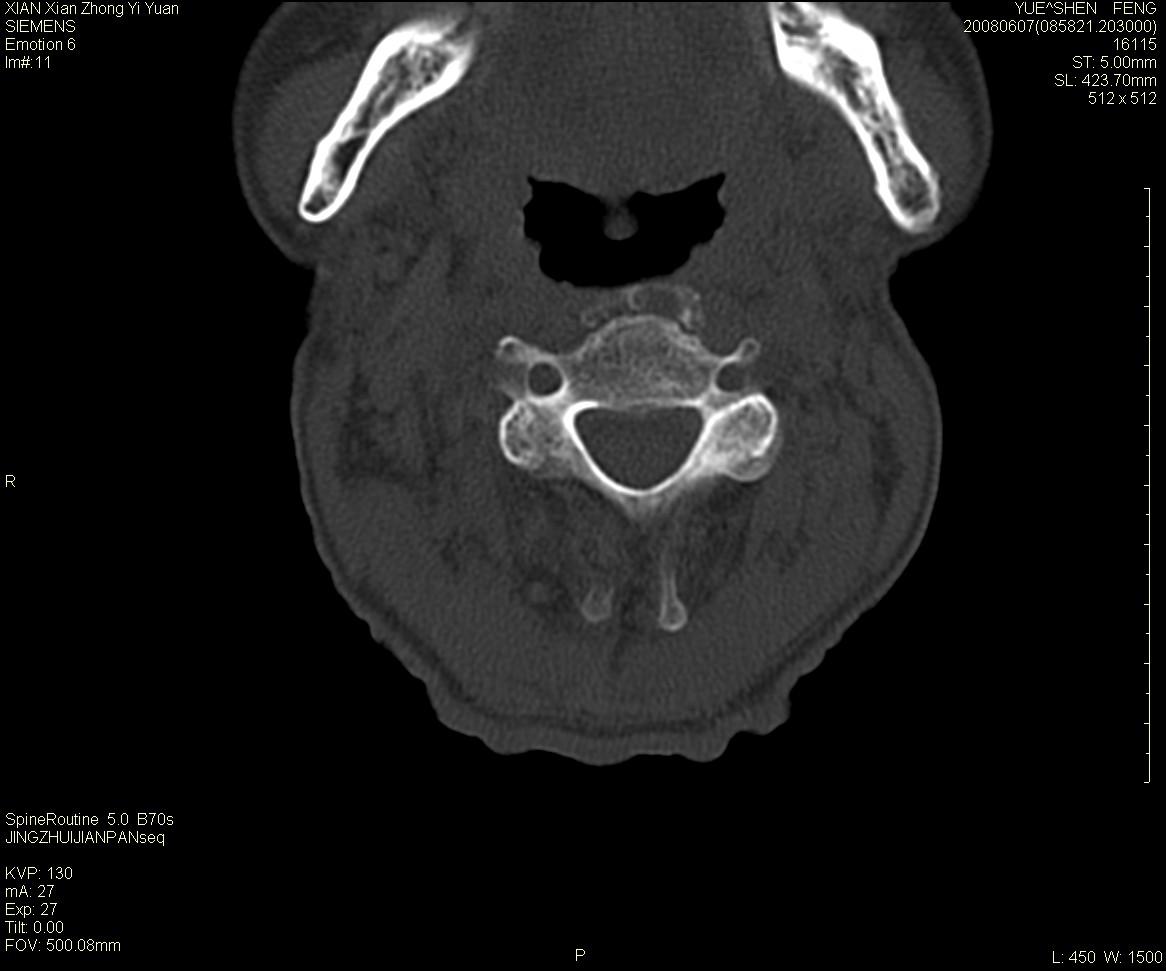

标题: CT13889:M72,颈部疼痛两年,近来加重。 [打印本页]

标题: CT13889:M72,颈部疼痛两年,近来加重。

枢椎囊状膨胀性改变,边缘锐利,周围无软组织肿块,考虑骨巨细胞瘤可能。转移瘤破坏膨胀性改变较轻。

作者: XIANXIANZHONGYI    时间: 2008-6-9 18:06

依据:

1 老年男性,颈部疼痛两年余。

2 ct:枢椎椎体显示膨胀性溶骨性骨质破坏,受损区域较大,边界清晰,其中似可见有小囊状结构,并残存有少量的骨小梁。病变与正常骨组织之间有一狭窄的分界区。受损部位部分边缘显示轻度骨质硬化。病灶突破骨皮质并在椎管形成软组织肿块影。

影像学检查:骨骼x线表现为单一部位的溶骨性改变,受损区域较大,边界清晰,其中可见有小囊状结构,少数可残存有少量的骨小梁。病变与正常骨组织之间有一狭窄的分界区。部分患者可见到病理性骨折,少数表现为受损部位的骨质硬化。ct和磁共振(mri)检查可以更加清晰地显示病损范围和性质以及周围软组织情况,并可能发现x线未显示的病灶以及更准确地判断骨髓是否受累。骨孤立性浆细胞瘤的ct和mri表现为扩张性溶骨性改变,骨质的破坏区完全被软组织肿块所代替,骨质膨胀,边界清晰,常突破骨皮质并在附近形成软组织肿块影。脊柱受累还可深入到锥管压迫神经束或神经根。